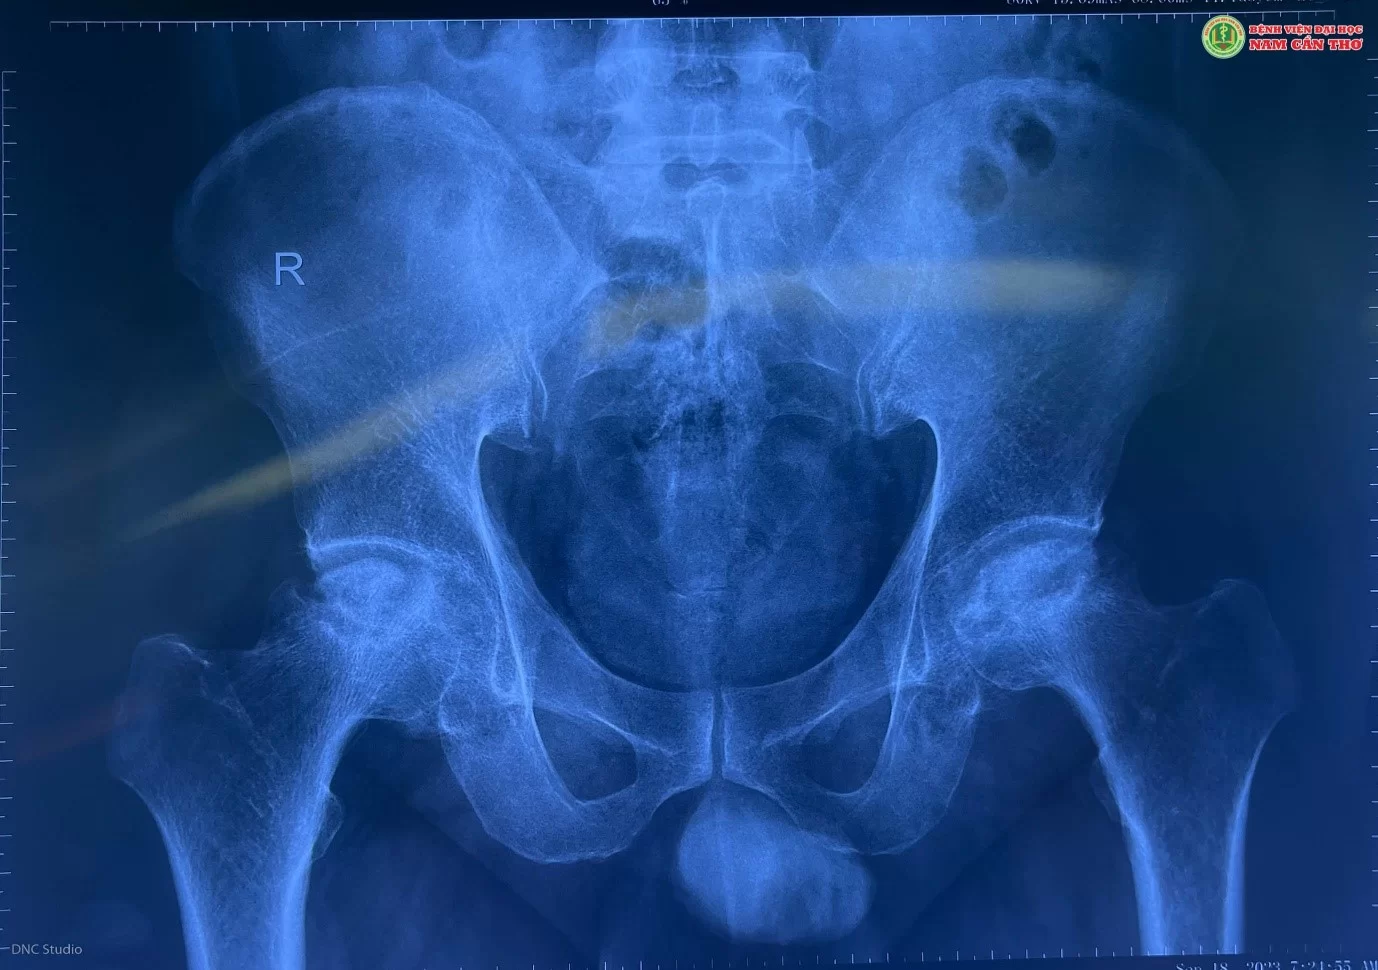

Tại Bệnh viện Đại học Nam Cần Thơ, anh T.T.K được Bác sĩ tại Khoa Ngoại tổng hợp và Tạo hình thẩm mỹ tiếp nhận, chẩn đoán anh K bị hoại tử chỏm xương đùi hai bên. Bác sĩ chỉ định anh K cần phẫu thuật thay khớp háng càng sớm càng tốt. Tuy lo lắng, nhưng sau khi được giải thích về những ưu điểm và kết quả điều trị của phương pháp thay khớp háng mang lại, anh K và gia đình đã đồng ý thực hiện phẫu thuật thay khớp háng.

Chỏm xương đùi bị hoại tử cần phải phẫu thuật thay khớp háng (Ảnh DNC Studio)